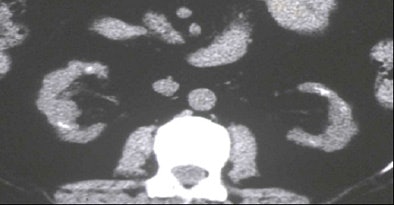

| Top to bottom: Indented kidneys with cysts typical of ESRD, but not 'SICK,' seen in a 61-year-old patient. All patients were imaged within three months of ESRD diagnosis and the beginning of dialysis, and yielded only subtle CT findings in most of them. All images courtesy of Lauren Brubaker. |

"We developed the acronym 'SICK' to indicate bilaterally small, indented, and calcified kidneys," she said. "In terms of radiological findings, as you would expect, we found small, smooth kidneys in 65% of our ESRD population. Other typical ESRD patterns were small kidneys with cysts, as well as kidneys with so many cysts they are causing indentations or scars within the kidneys. Contour was assessed for calcification through scars, as well as calcifications for size and location."